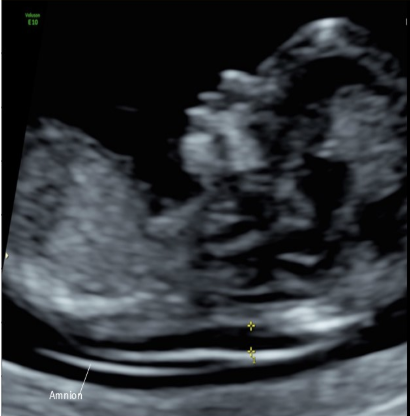

a pt at 36w for cervical length measurement. she says she has been leaking amniotic fluid for the last few hours.

how should the cervical evaluation be performed

a) TV approach, empty bladder, sag image

b) cervical measurement cannot be performed on this pt

c) TA approach, moderate bladder distension, sag image

d) translabial approach, empty bladder, sag image